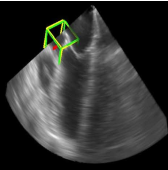

利用2891次心脏超声检查的数据集,Ghesu等结合深度学习和边缘空间学习进行医学图像检测和分割[12]。“大参数空间的有效探索”和在深度网络中实施稀疏性的方法相结合,提高了计算效率,并且与同一组发布的参考方法相比,平均分割误差减少了13.5%,八位患者的检测结果如图4所示。Brosch等人利用MRI图像上研究多发性硬化脑病变分割的问题。开发了一种3D深度卷积编码器网络,它结合了卷积和反卷积[13],图5.增加网络深度对病变的分割性能的影响。卷积网络学习了更高级别的特征,并且反卷积网络预进行像素级别分割。将网络应用于两个公开的数据集和一个临床试验数据集,与5种公开方法进行了比较,展现了最好的方法。Pereira等人的研究中对MRI上的脑肿瘤分割进行了研究,使用更深层的架构,数据归一化和数据增强技巧[14]。将不同的CNN架构用于肿瘤,该方法分别对疑似肿瘤的图像增强和核心区域进行分割。在2013年的公共挑战数据集上获得了最高成绩。

图4示例图像显示了不同患者的检测结果从测试集。检测到的边界框以绿色显示,标准的框以黄色显示。原点位于每个框中心的线段定义相应的坐标系